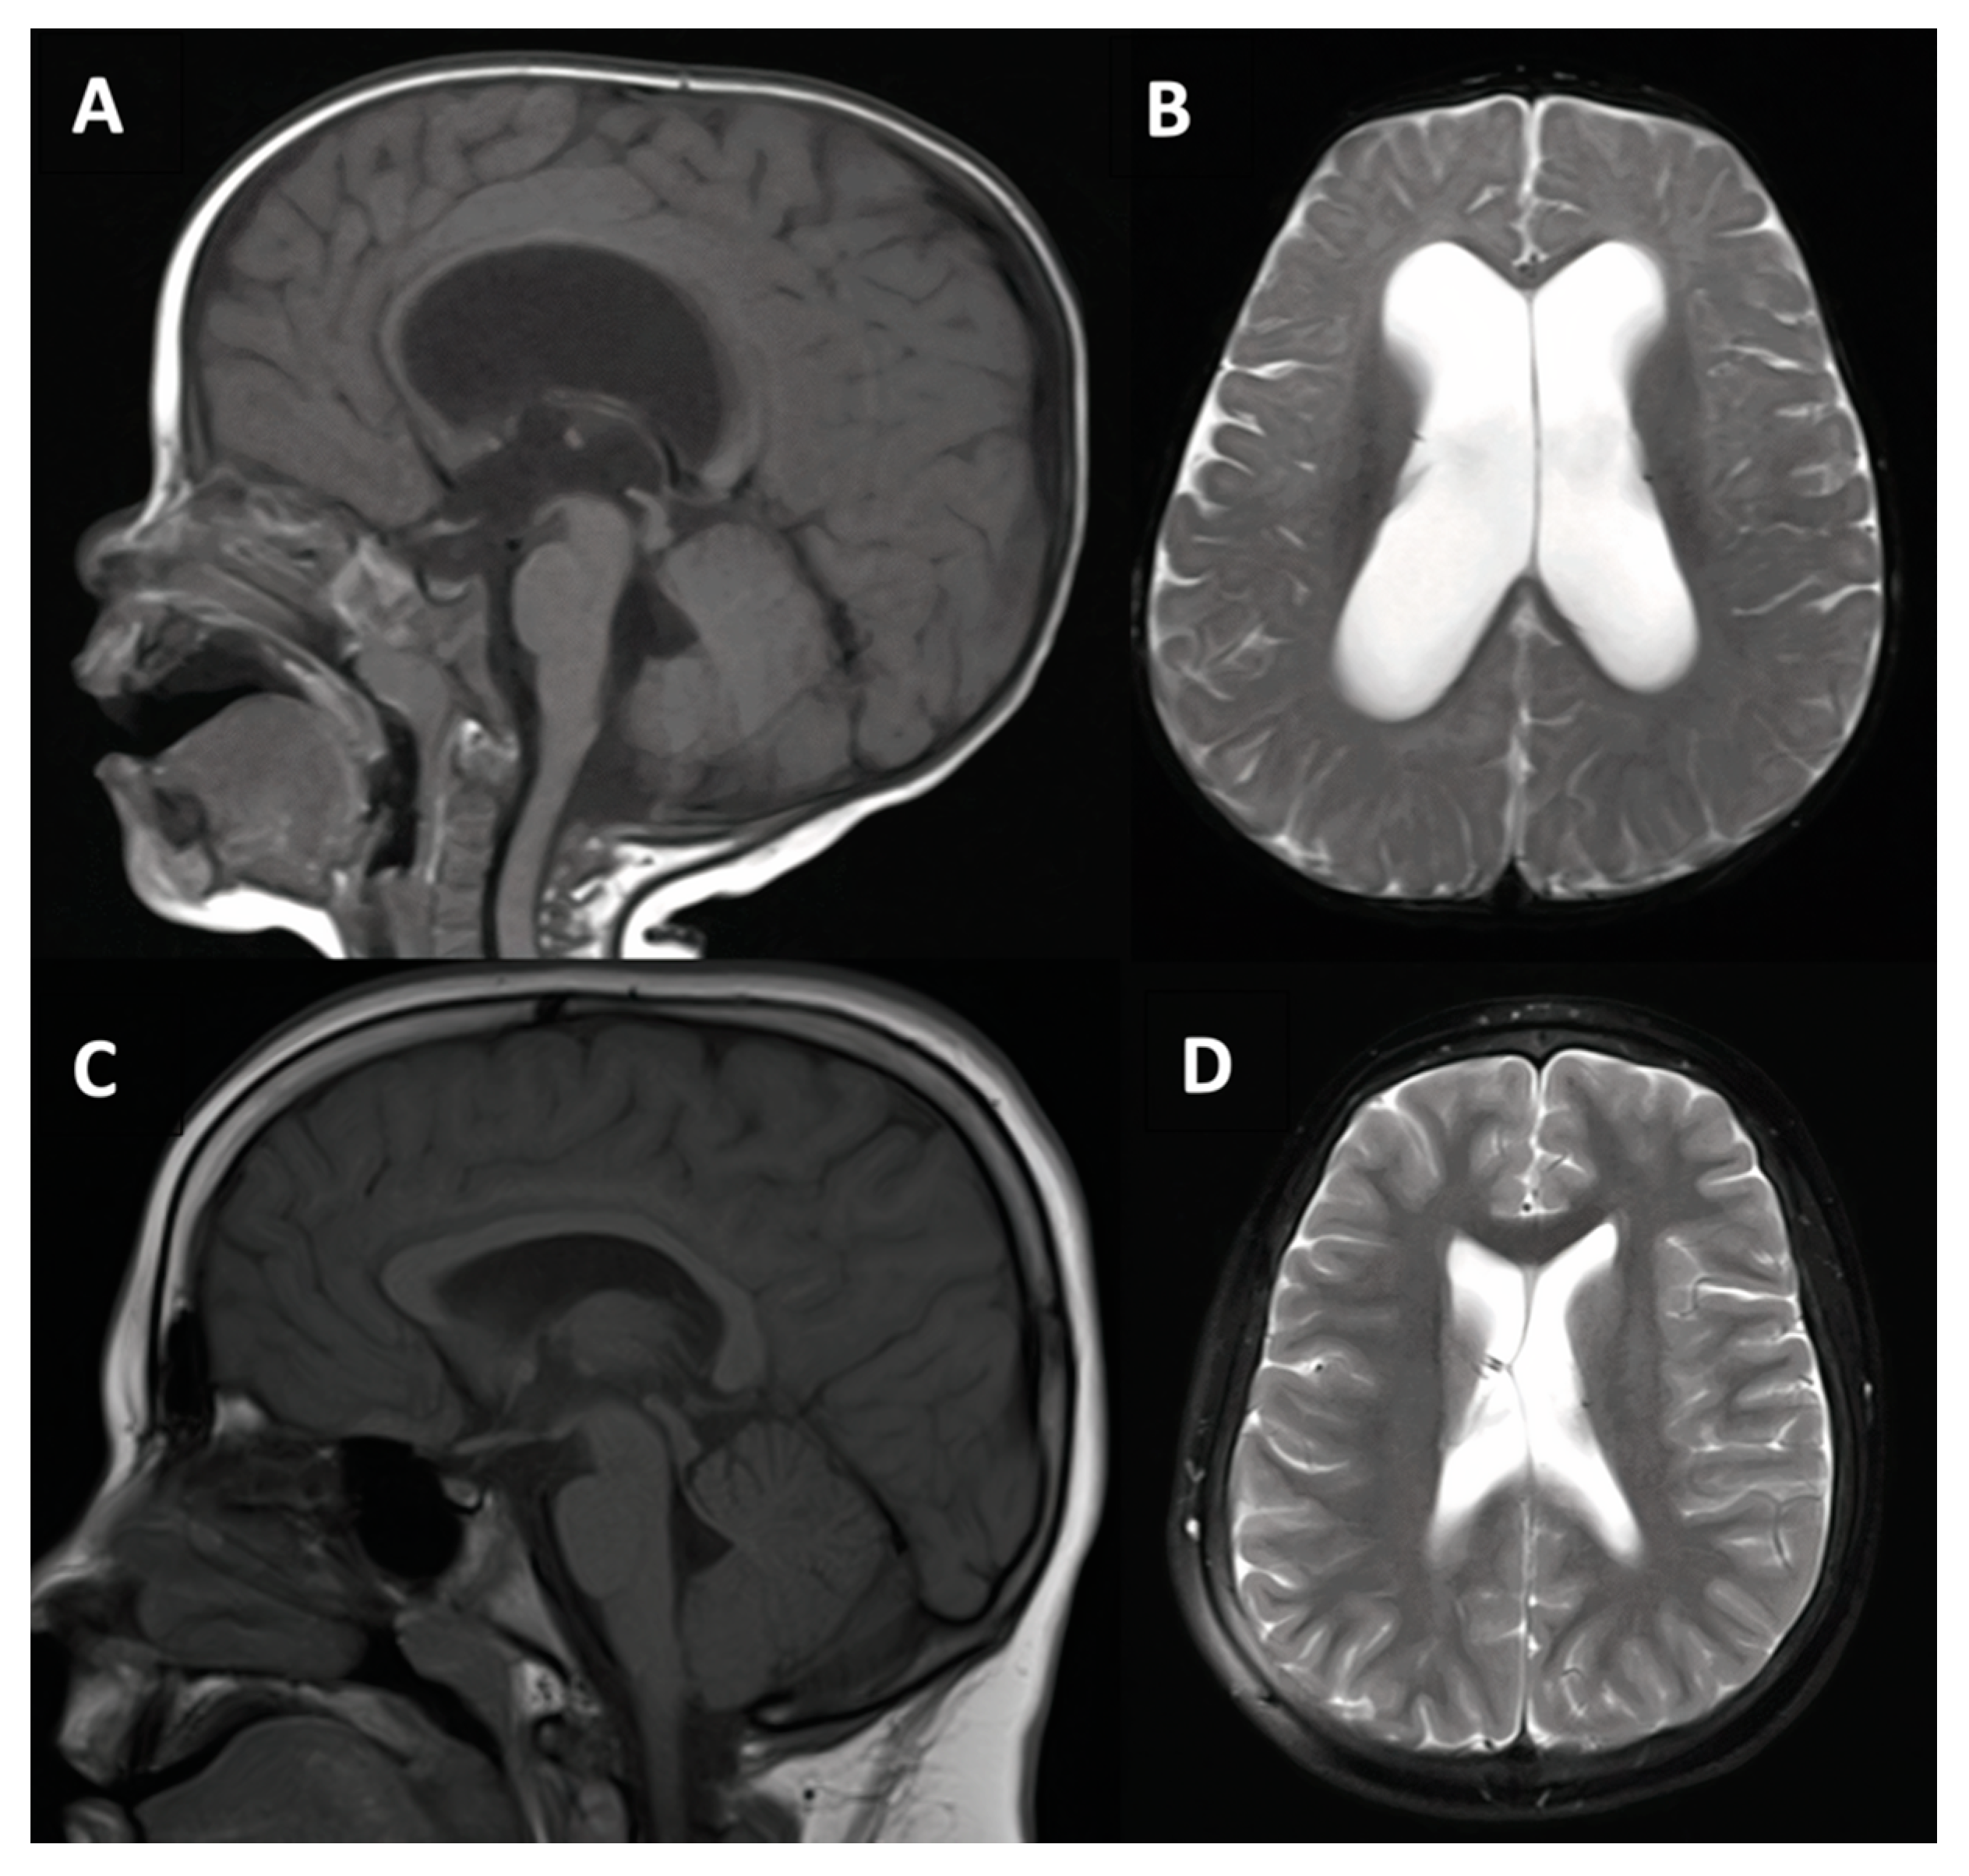

3.1.2. Case #2. Congenital Hydrocephalus with Cerebral Palsy

| 2 | 17 m, M |

|